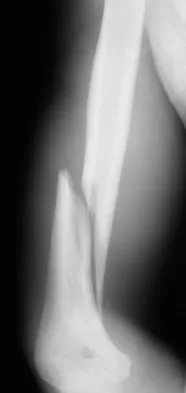

A 58-year-old woman is seen in the emergency department after falling at home. History reveals that she underwent right total knee arthroplasty 2 years ago. Radiographs are shown in Figures 56a and 56b. What is the most appropriate treatment?

Correct Answer: Open reduction and internal fixation

Explanation:

The radiographs show an oblique periprosthetic distal femoral fracture. Of the options listed, open reduction and internal fixation is the most appropriate surgical option because a well-fixed, posterior stabilized closed box femoral component is present. Nonsurgical methods are not favored because of the highly displaced, unstable fracture pattern and prolonged immobility. Revision with a stemmed component is an option but would sacrifice more bone stock in this younger patient. Moran MC, Brick GW, Sledge CB, et al: Supracondylar femoral fracture following total knee arthroplasty. Clin Orthop 1996;324:196-209. Raab GE, Davis CM III: Early healing with locked condylar plating of periprosthetic fractures around the knee. J Arthroplasty 2005;20:984-989.